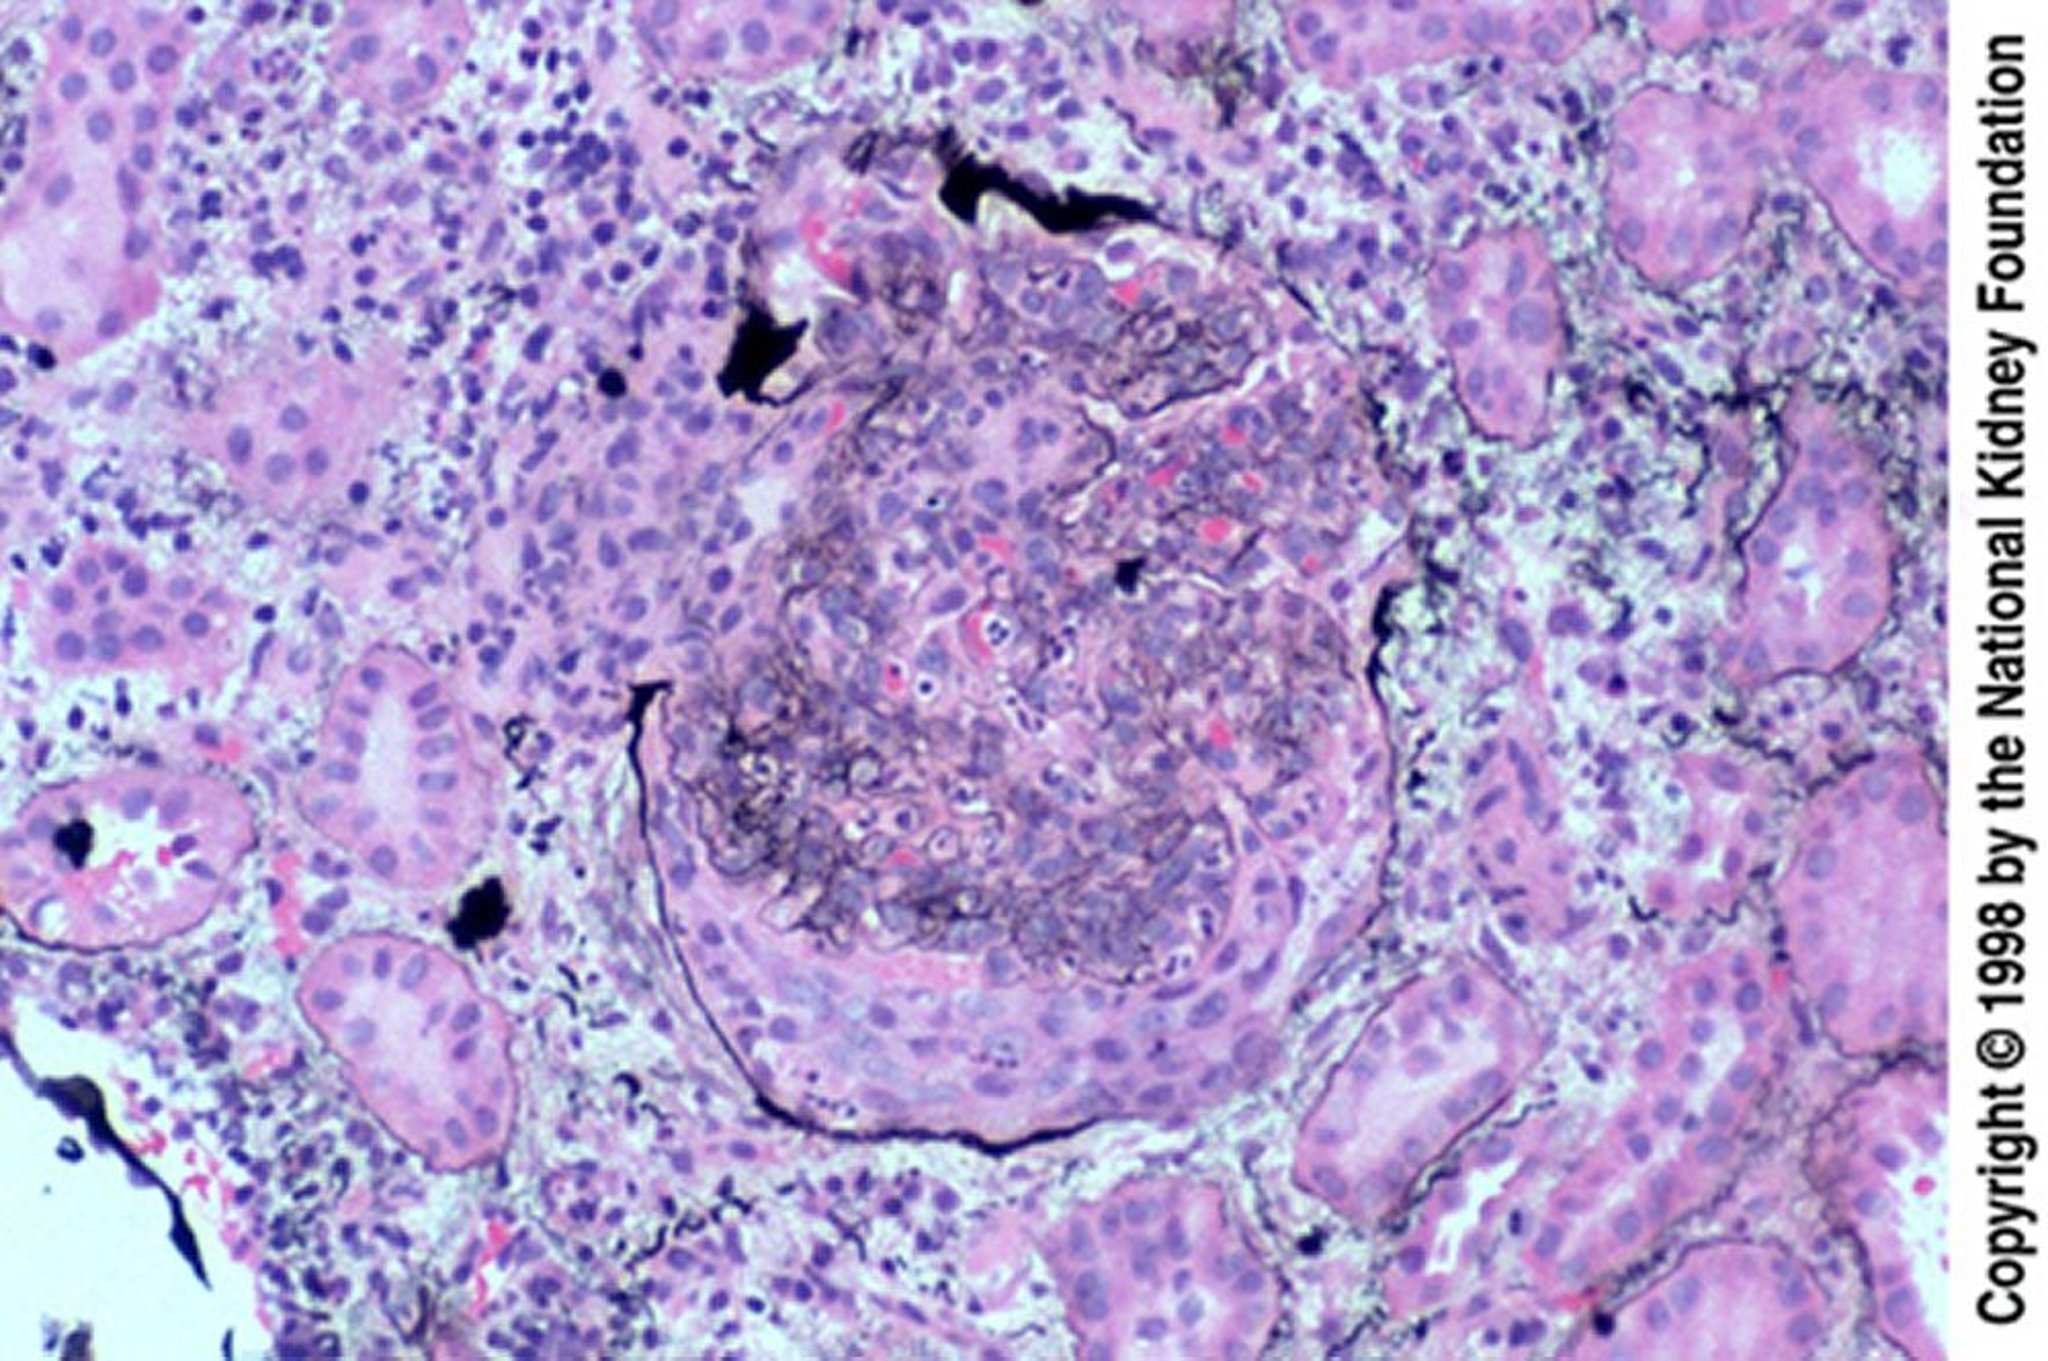

感染後糸球体腎炎(上皮半月体形成)

上皮半月体形成は,治療効果がみられずに後になって生検が施行された場合に特によくみられる。半月体によりボーマン嚢が破裂している(PAM染色,200倍)。

Image provided by Agnes Fogo, MD, and the American Journal of Kidney Diseases' Atlas of Renal Pathology (see www.ajkd.org).